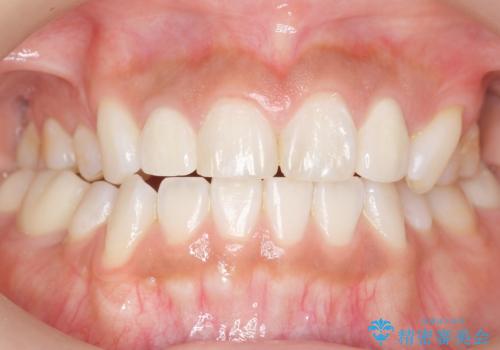

- 奥歯の隙間を治したいとご希望された患者様です。

学生時代に舌側矯正されていたものの、通院が大変になり治療を途中でやめてしまい、奥歯の間に隙間が残ってしまったそうです。

矯正せずに早く治したいという強いご希望とう蝕があることから、セラミッククラウンによる補綴治療で隙間を閉じることにしました。

矯正せずに隙間を閉じることができ、ご満足頂けました。

セラミッククラウンの審美的な仕上がりと咬み心地に喜んで下さいました。